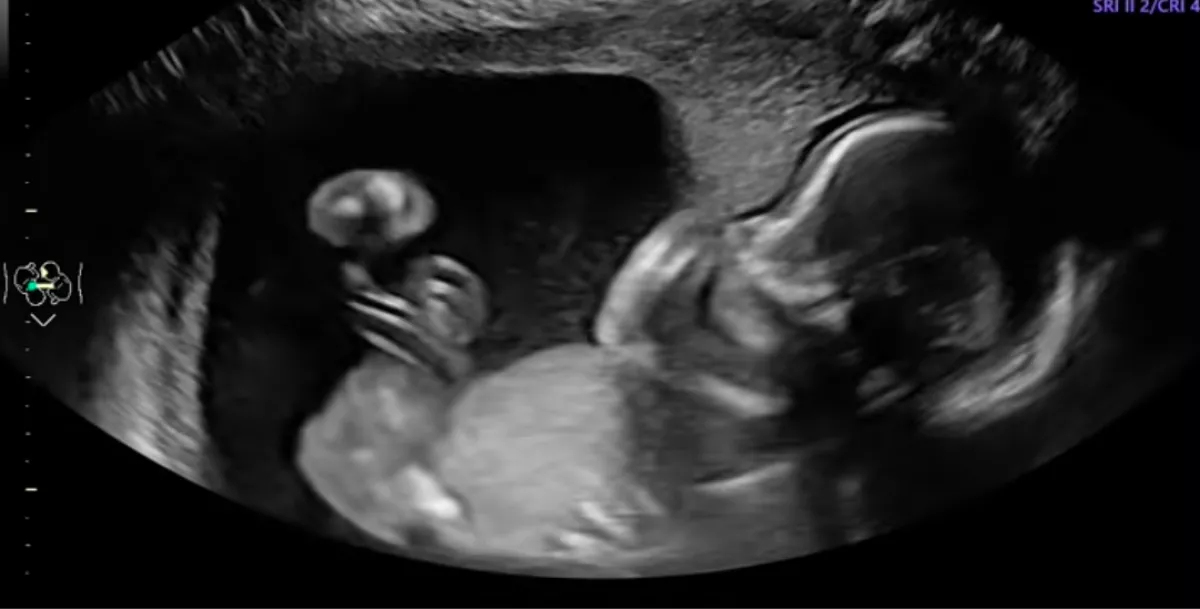

Mara McCoy akkoriban a terhessége 20. hetében volt, azaz a várandóssága felénél járt. Ő és férje, Terrance egy rutinvizsgálaton vettek részt, ahol ultrahangvizsgálatot is végeztek. A pár nagyon meghatódott, amikor megpillantották lányukat, aki valószínűleg még körülbelül 20 hétig fog növekedni a nő méhében. Ami ezután történt, az egyrészt lett váratlan, másrészt látható és kézzelfogható volt.

A klipben látható, ahogy a születendő gyermek kezdetben nyugodt marad az ultrahangvizsgálat során, amíg hirtelen ököllel meglendíti az anyja hasfalát belülről. „Ez nem mesterséges intelligencia” – teszi hozzá a várandós nő, biztosítva nézőit: ez tényleg megtörtént!